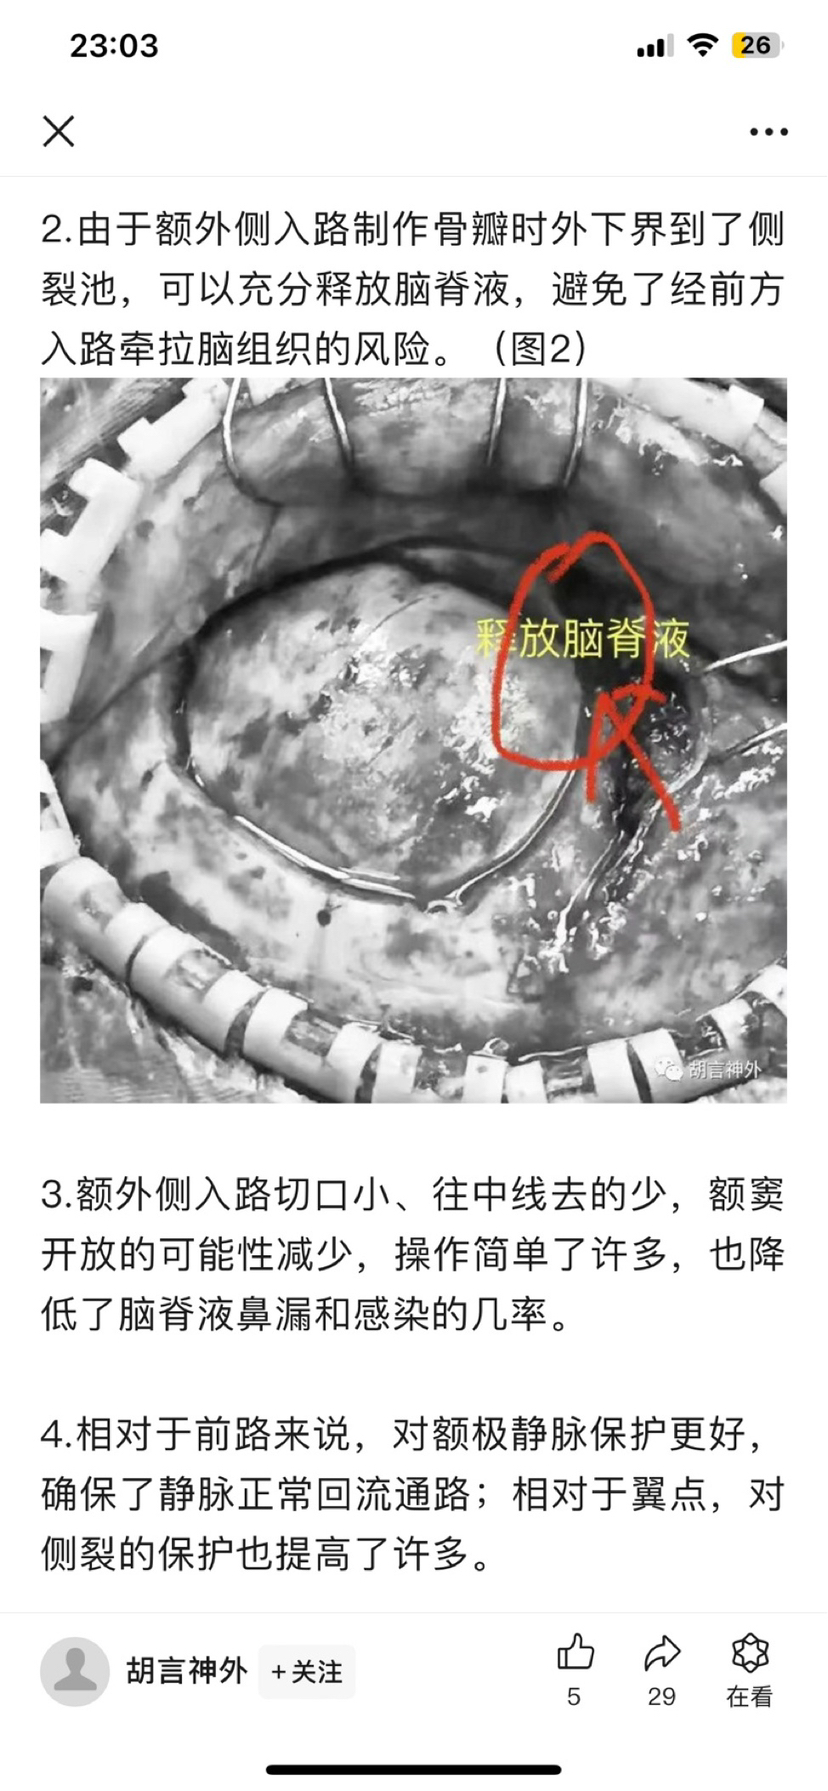

开颅术前参考文献阅读

为方便大家查找原文,特备注公众号信息:2022年03月05日 注册“胡言神外”2025年02月27日 “胡言神外”改名“胡言之言”。(声明:截图分享纯为方便交流,如有侵权或对作者有不良影响,请联系进行相关内容删除,谢谢!)